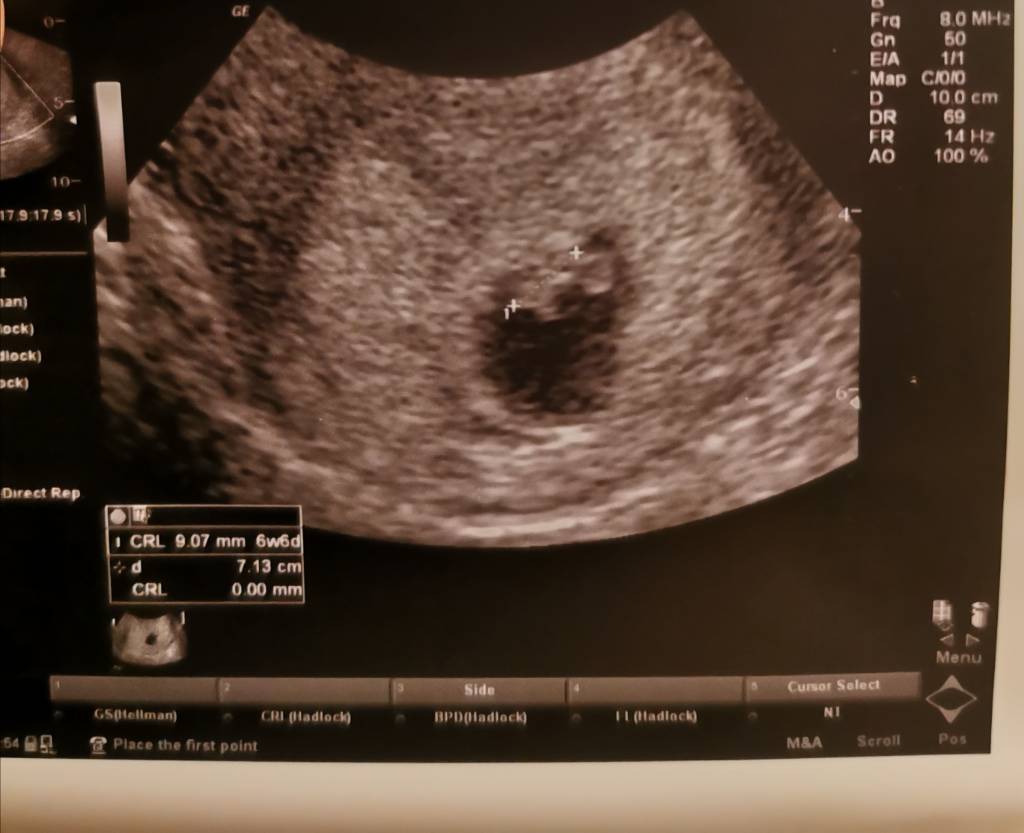

Mamy pieknego, prawie centymetrowego Bobika z sercem jak dzwon

. Według om 7+1 a według dziecka 6+6. Mój mąż uparł sie, ze chce chodzić na każde badanie. Dzis tez byl. Lekarz robil mi usg dopochwowe i znalazl pecherzyk a za chwilę powiedział, ze jest jeszcze jeden. Moj maz zrobil sie blady jak ściana i powiedział"co?!". A lekarz pytal czy to z ekscytacji czy z przerażenia

. Powiedział, ze nie do konca jest pewien bo mam pełen pęcherz i padaja cienie. Po powrocie z usg potwierdził ciążę pojedynczą więc odetchnelismy